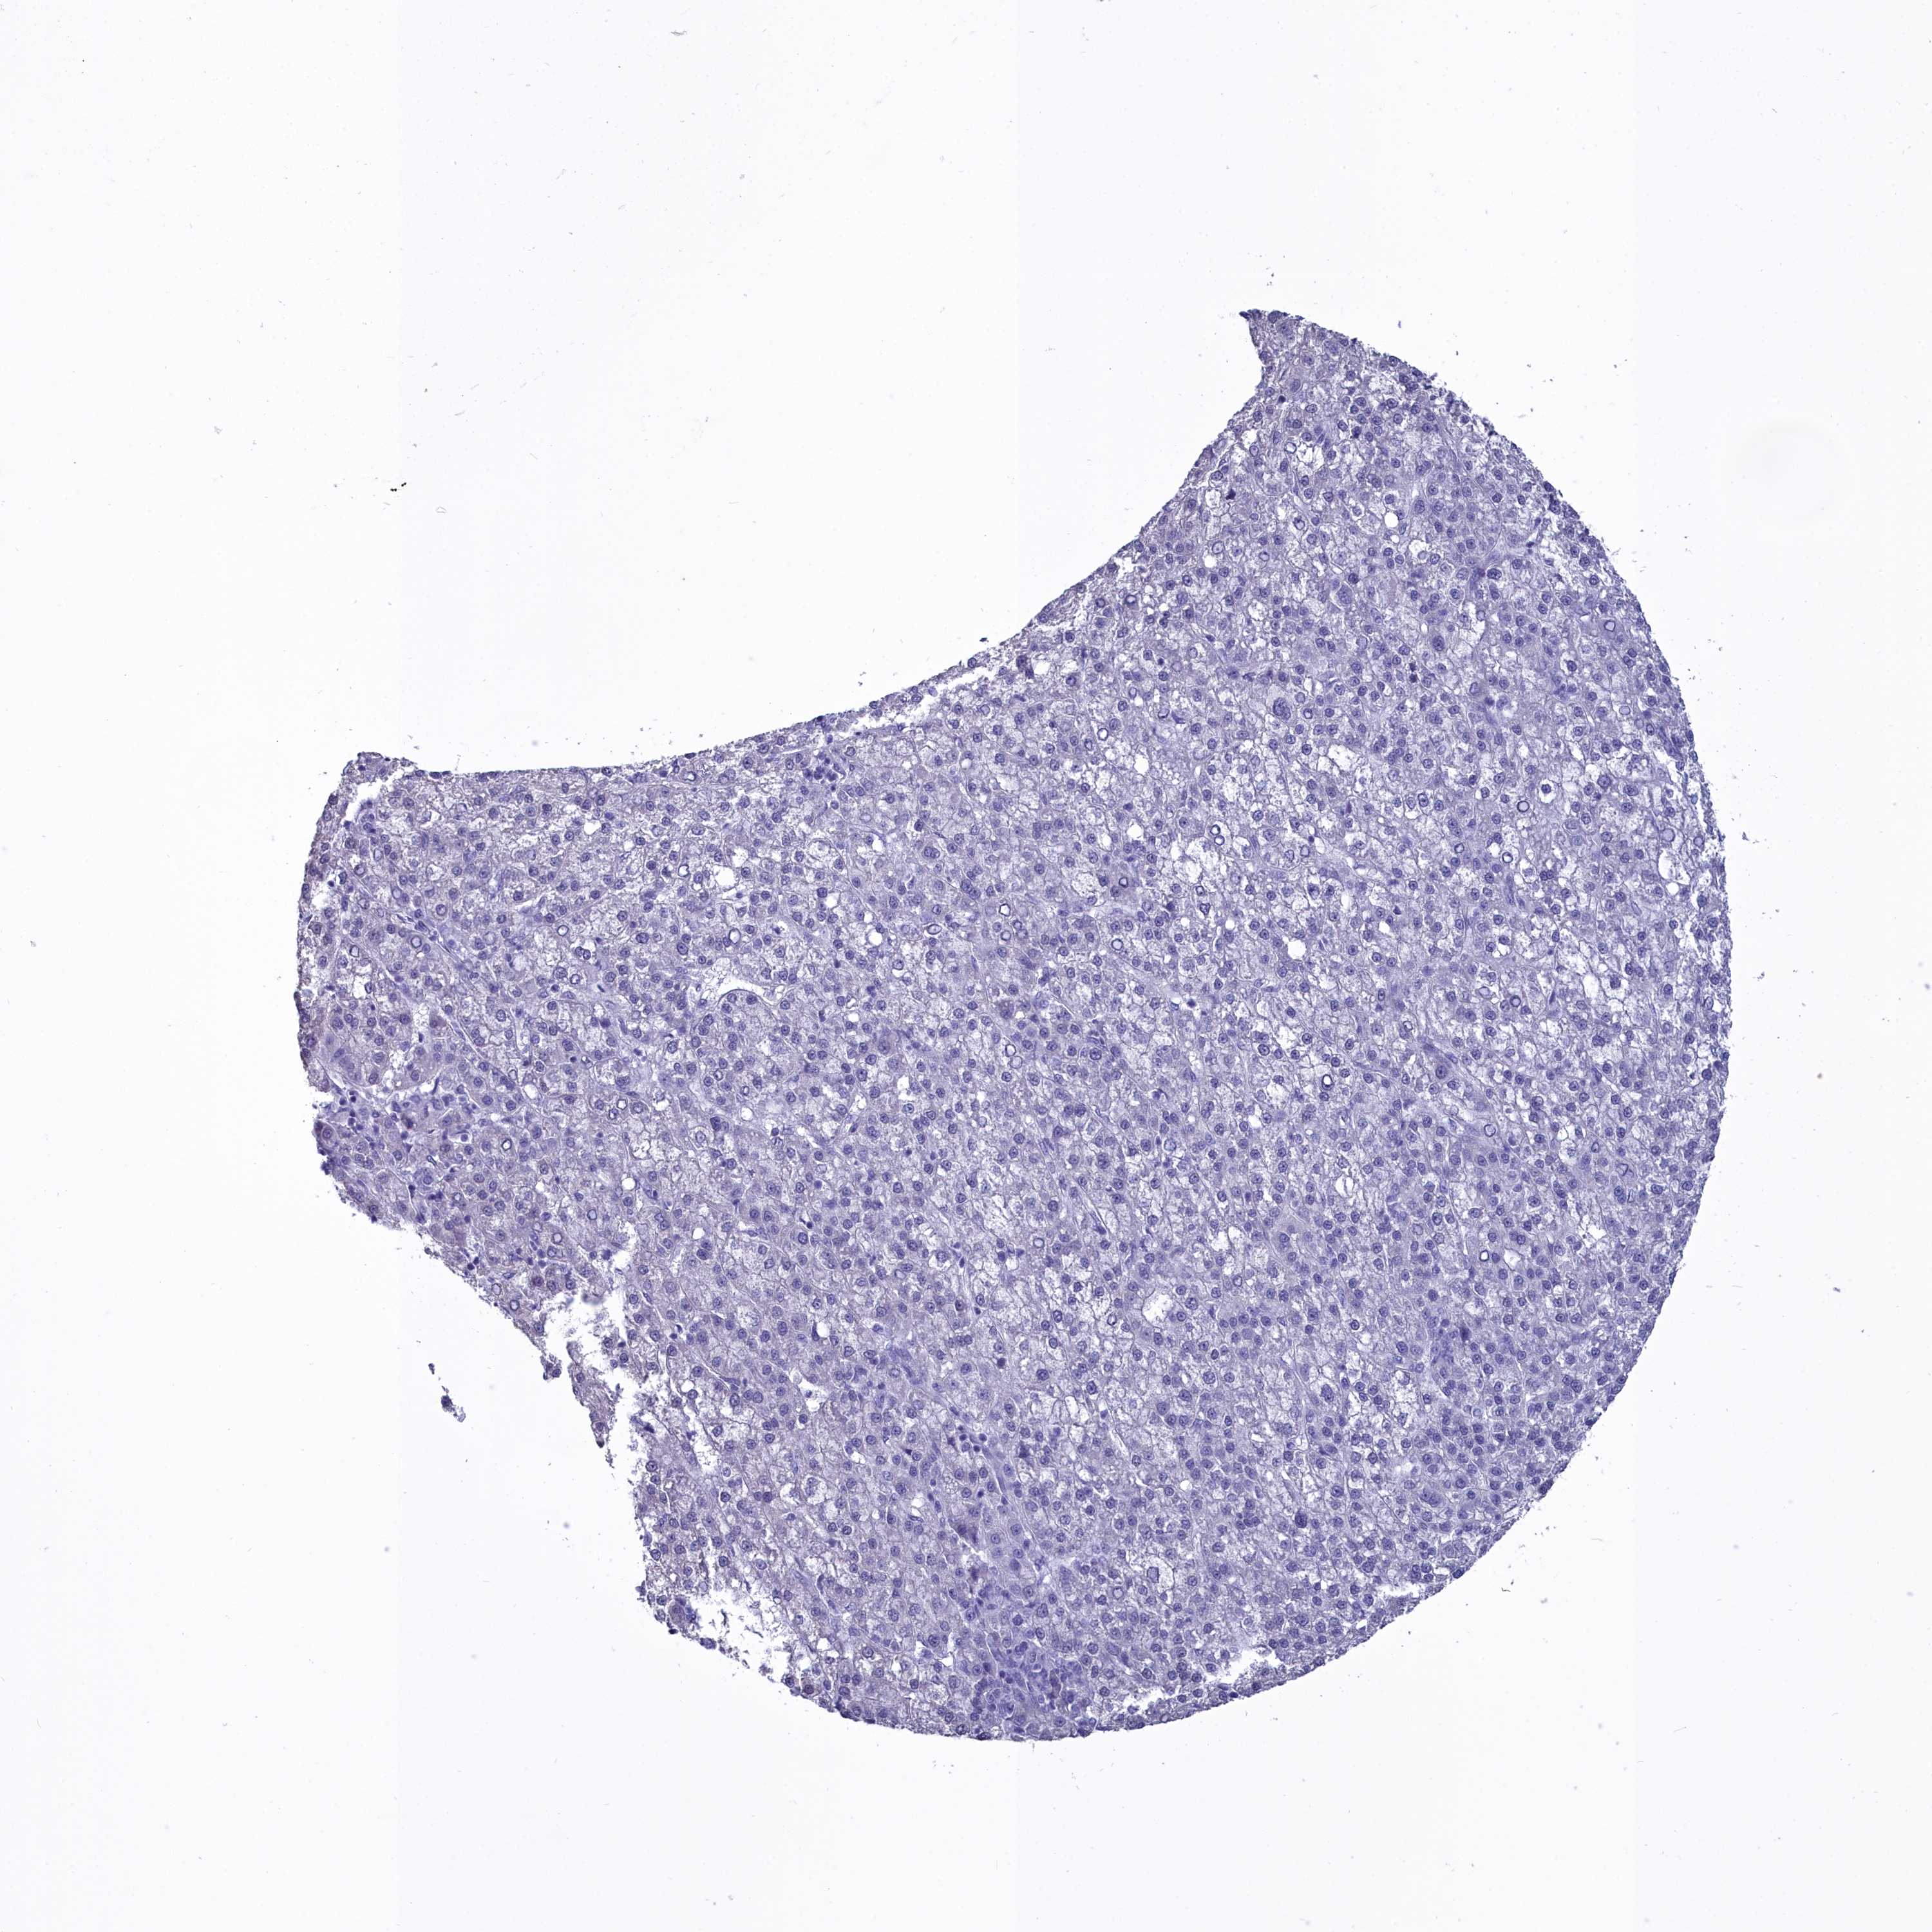

LIVER CANCER - Protein expressioni

A mouse-over function shows sample information and annotation data. Click on an image to view it in a full screen mode. Samples can be filtered based on level of antibody staining by selecting one or several of the following categories: high, medium, low and not detected. The assay and annotation is described here.

Note that samples used for immunohistochemistry by the Human Protein Atlas do not correspond to samples in the TCGA dataset.

Antibody stainingi

Antibody staining in the annotated cell types in the current human tissue is reported as not detected, low, medium, or high, based on conventional immunohistochemistry profiling in selected tissues. This score is based on the combination of the staining intensity and fraction of stained cells.

Each image is clickable and will lead to virtual microscopy that enables deeper exploration of all samples and also displays staining intensity scores, fraction scores and subcellular localization as well as patient and tissue information for each sample.

Antibody HPA039061

Antibody HPA039062

Antibody CAB015442

Antibody CAB022600

Cholangiocarcinoma

Carcinoma, Hepatocellular, NOS